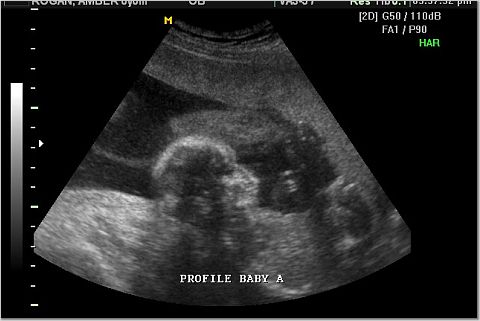

Baby A was the active one. Here is her profile and her hand.